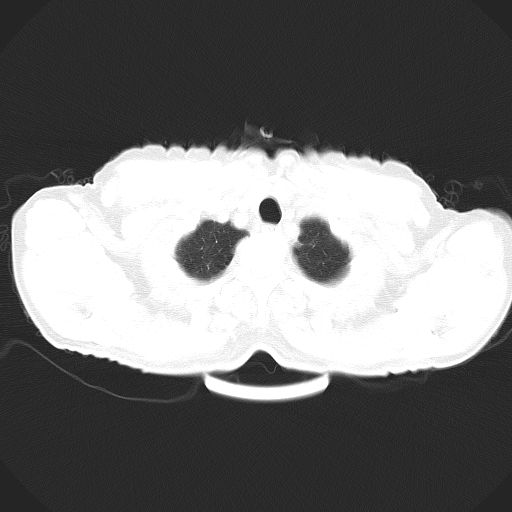

以下是引用心路寻觅在2010-3-1 10:23:00的发言:[br]1、考虑左肺上叶周围型肺癌[br]2、右上肺陈旧性病灶。[br][br][本贴已被 心路寻觅 于 2010-3-1 10:40:18 修改过]

以下是引用shuiyuan在2010-3-1 10:45:00的发言:[br]考虑左肺上叶中心型肺癌伴阻塞型炎症,邻近胸膜受侵。